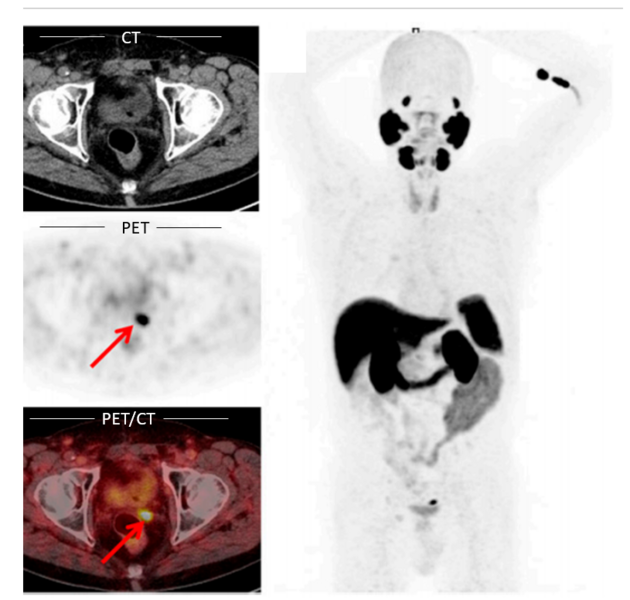

PSMA-PET/CT

PSMA-PET/CT ist eine tumorspezifische (rezeptorspezifische) Diagnostik, bei der der PSMA-Ligand Prostata-Tumorzellen im Körper detektiert und unter Verwendung der PET-Technik diese dargestellt. Zu dieser Untersuchung müssen Sie nicht nüchtern erscheinen. Die Unterlagen zu Ihrem bisherigen Krankheitsverlauf sowie evtl. die Bilder der früher durchgeführten radiologischen und nuklearmedizinischen Untersuchungen (CT-, PET/CT-Bilder auf CD) sind wichtig für die Untersuchung. Insbesondere sind folgende Informationen hilfreich für uns:

·Diagnose sowie Krankheitsverlauf: Aktueller Arztbrief mit Krankheitsverlauf und relevanten Vorerkrankungen; bitte Informationen über relevante Vor-OPs (radikale Prostatektomie, Lymphadenektomie, etc.), Bestrahlungen, Hormontherapie, etc.).

·OP-Bericht

·Histologie-Bericht (mit Gleason-Score)

·Vorherige bildgebende Verfahren mit CD und Bericht (z.B. CT- oder MRT-Voruntersuchungen, Skelettszintigrafien, etc.)

·Verlaufswerte des PSA-Wertes:

-Initialer PSA mit Datum

-Niedrigster PSA-Wert im Krankheitsverlauf (z.B: nach OP oder nach Bestrahlung) mit Datum

-Aktueller PSA-Wert

Darüber hinaus sind die aktuellen Schilddrüsen- und Nierenwerte (TSH und Kreatinin) notwendig, damit die Untersuchung mit Kontrastmittel durchgeführt werden kann. Diese Werte sollten nicht älter als 14 Tage sein.